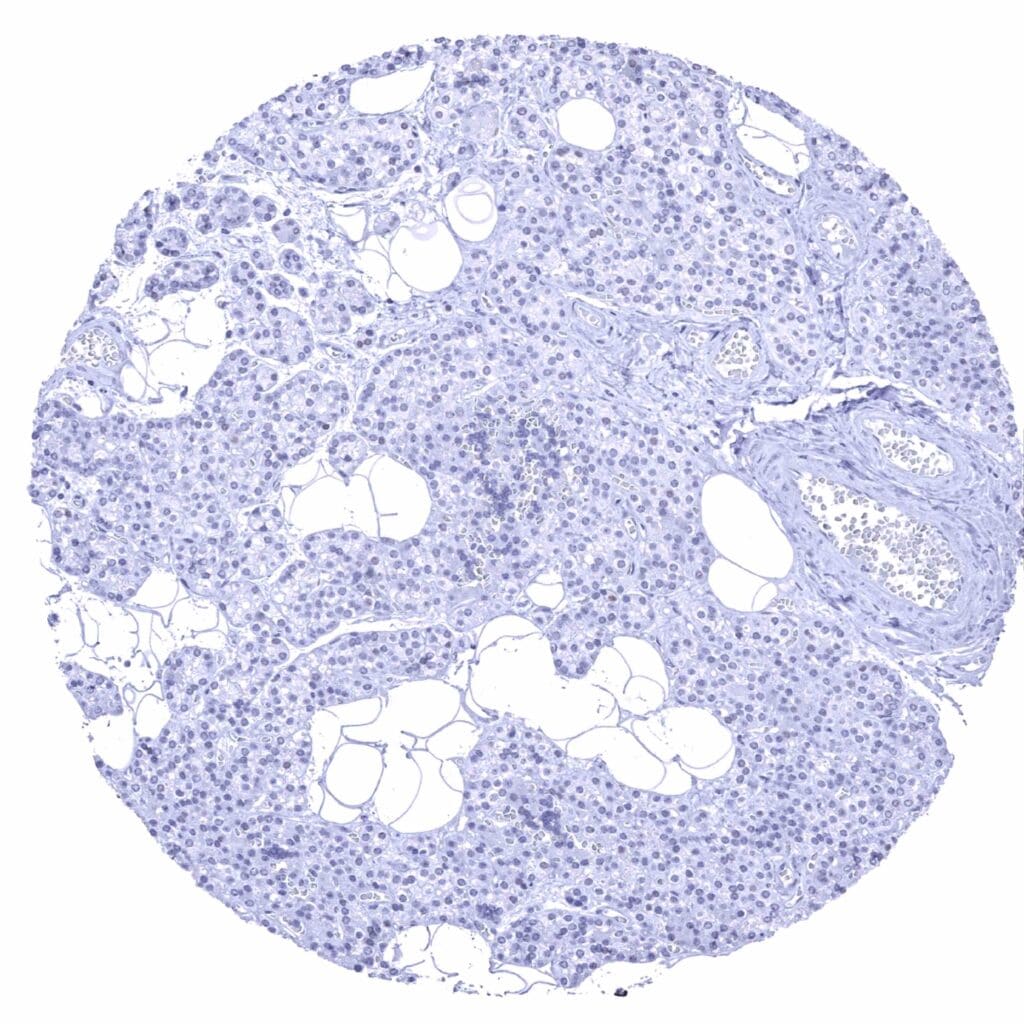

Lymph node – A fraction of lymphocytes from the germinal centre show a faint nuclear p53 staining (p53 immunohistochemistry).